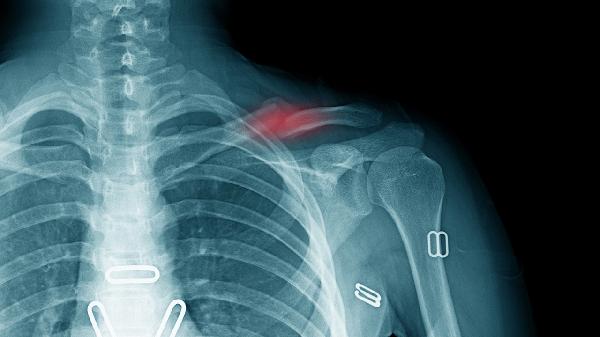

Smith骨折和Barton骨折是两种不同的腕部骨折类型,主要区别在于骨折位置和损伤机制。Smith骨折是桡骨远端向掌侧移位,Barton骨折是桡骨远端关节面骨折伴腕关节脱位。

Smith骨折通常发生在跌倒时手背伸位着地,导致桡骨远端向掌侧移位。这种骨折可能伴随腕关节不稳定和正中神经损伤。患者会出现腕部疼痛、肿胀和活动受限。治疗上可采用手法复位石膏固定,严重时需手术内固定。

Barton骨折分为掌侧型和背侧型,掌侧型更为常见。这种骨折涉及桡骨远端关节面,常由高能量创伤引起。患者除腕部疼痛肿胀外,还可能出现关节畸形。由于涉及关节面,通常需要手术复位固定以恢复关节平整度。